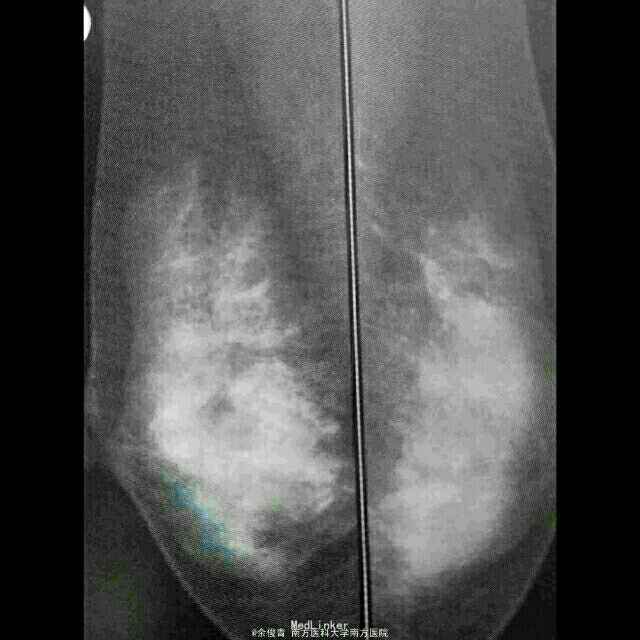

患者,女,50岁,乳腺体检时发现双乳多发钙化

查体:未及明显异常。 辅助检查:超声未发现明显异常,可见多个大小约0.3-0.5cm低回声区,乳腺增生明显。 钼靶:双乳上方多发散在分布的细小钙化,钙化大小密度不均,建议定期随访或切取活检。

诊断:乳腺良性钙化 治疗:局麻下行双乳钙化灶切取活检术,术后病理示:乳腺纤维囊性乳腺病伴导管内钙化。